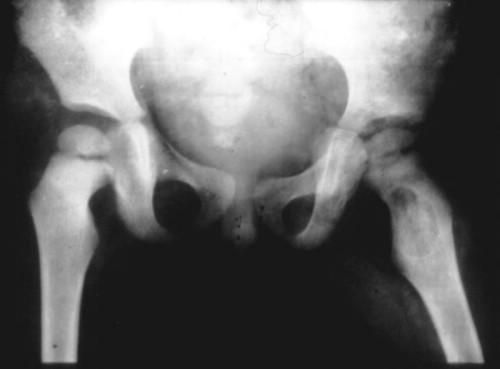

♥骨与关节结核

♥X片描述

۞ 骨与关节结核的X片描述